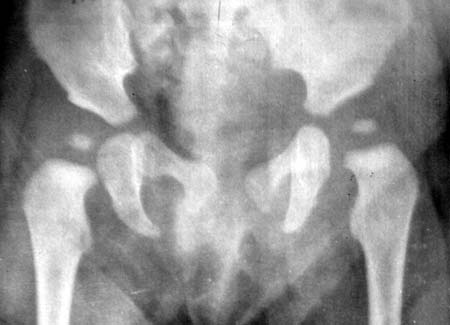

标题: PED0495:髋脱位治疗复查对比

第一副图象是治疗前的 第二副图象是治疗后的 前后时间相差6个月

前后两张片子左右没弄混吧?第一张右髋沈通氏线较左侧差,第二张反之。半年时间小儿的骨头(闭孔、股骨头骨骺)长得挺快的。

若片子没有搞错,治疗效果应该是很好!